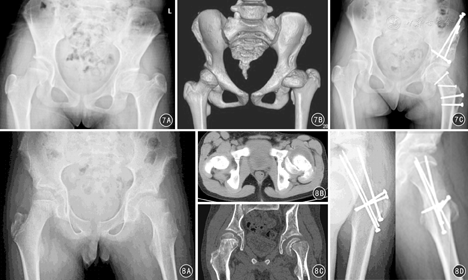

对股骨头颈部严重畸形,如股骨头骨骺滑脱、大头畸形等病变,在深入研究股骨头血液供应的临床解剖基础上,Ganz等[8,9]在SHD的基础上进一步推出了股骨颈软组织瓣延长技术(图6)。为处理股骨头复杂情况,研究者又开展了股骨头缩小成型术(图7)、股骨颈相对延长术(图7)、股骨头骨骺滑脱复位术(图8)等技术[22,23,24,25]。股骨颈软组织瓣延长技术的手术操作要点是:在SHD基础上,对大转子后侧突出部分的骨质进行骨膜内剥离、摘除,将股骨颈骨膜连同大转子后方的软组织瓣一同充分游离和松解,避免在对股骨头进行操作时MFCA过度牵拉造成股骨头缺血。然后在矢状面对股骨头缩小截骨成形、在股骨头颈交界处进行股骨头的内翻/外翻截骨以及对严重股骨头骨骺滑脱进行复位,避免继发撞击征和髋骨关节炎形成[13,14]。